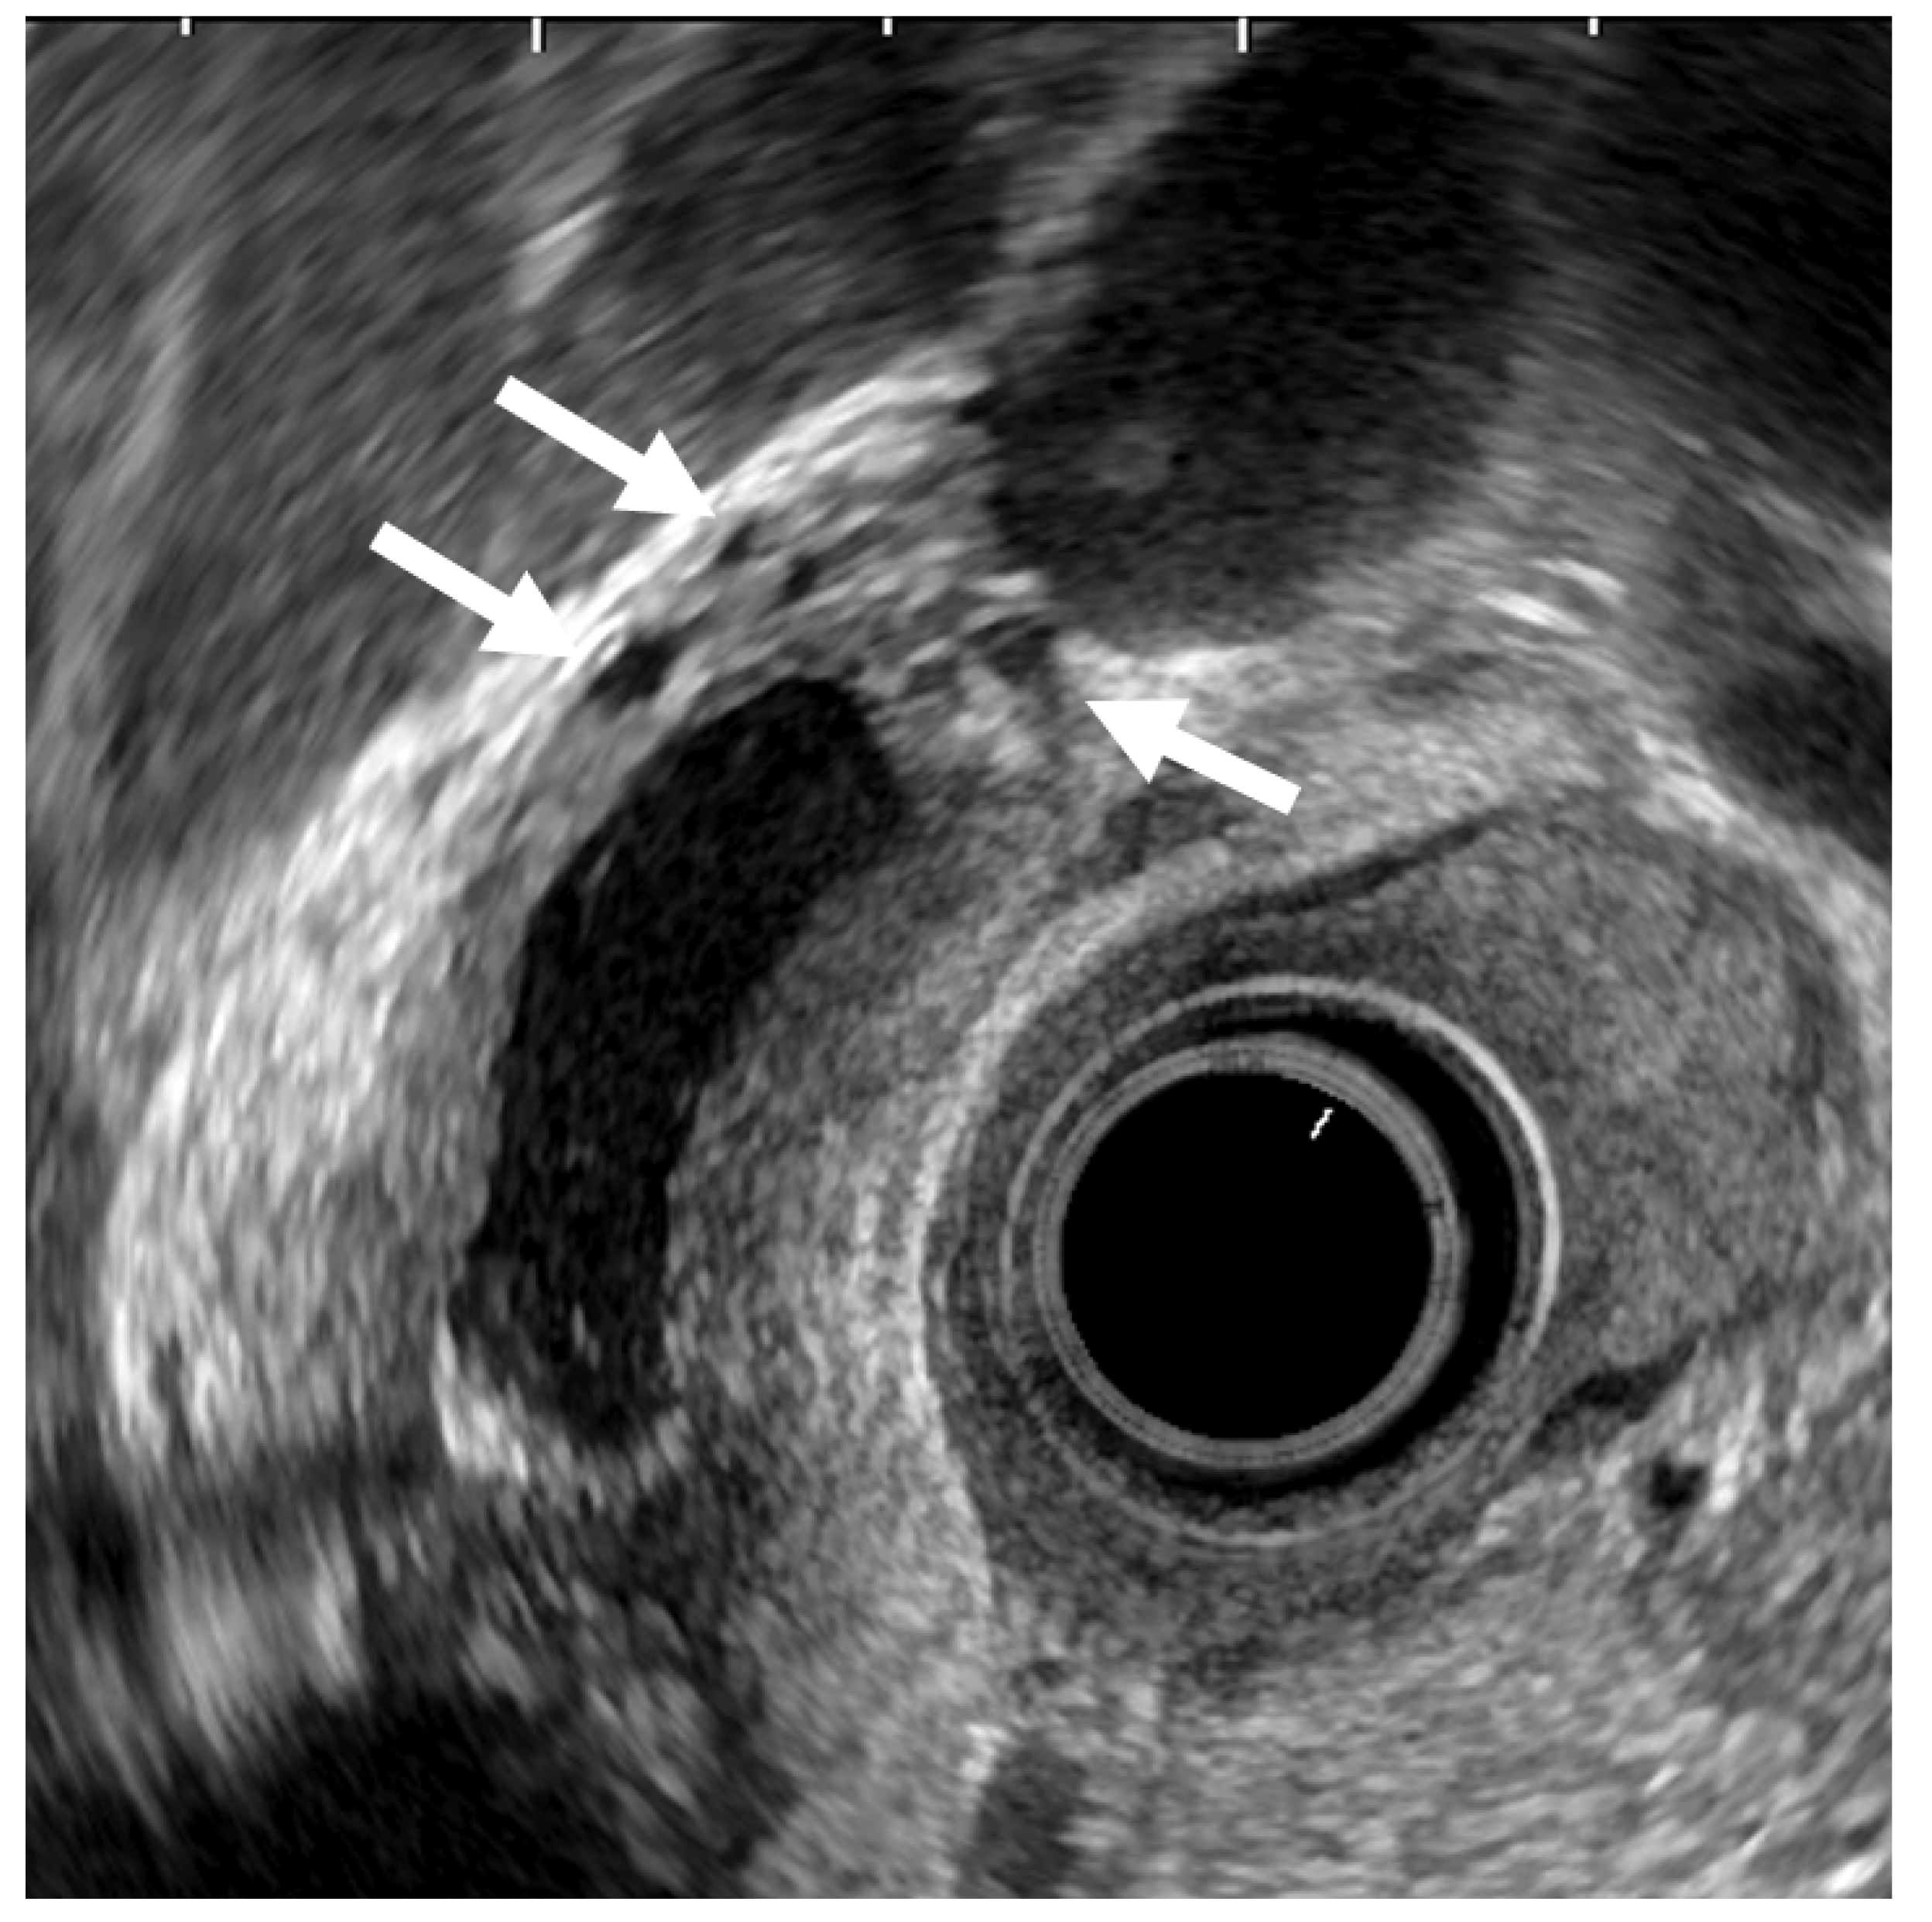

- Mizuguchi, M.; Kudo, S.; Fukahori, T.; Matsuo, Y.; Miyazaki, K.; Tokunaga, O.; Koyama, T.; Fujimoto, K. Endoscopic ultrasonography for demonstrating loss of multiple-layer pattern of the thickened gallbladder wall in the preoperative diagnosis of gallbladder cancer. Eur. Radiol. 1997, 7, 1323–1327. [Google Scholar] [CrossRef] [PubMed]

- Kim, H.J.; Park, J.H.; Park, D.I.; Cho, Y.K.; Sohn, C.I.; Jeon, W.K.; Kim, B.I.; Choi, S.H. Clinical usefulness of endoscopic ultrasonography in the differential diagnosis of gallbladder wall thickening. Dig. Dis. Sci. 2012, 57, 508–515. [Google Scholar] [CrossRef] [PubMed]

- Mitake, M.; Nakazawa, S.; Naitoh, Y.; Kimoto, E.; Tsukamoto, Y.; Asai, T.; Yamao, K.; Inui, K.; Morita, K.; Hayashi, Y. Endoscopic ultrasonography in diagnosis of the extent of gallbladder carcinoma. Gastrointest. Endosc. 1990, 36, 562–566. [Google Scholar] [CrossRef]

- Fujita, N.; Noda, Y.; Kobayashi, G.; Kimura, K.; Yago, A.; Mochizuki, F. Analysis of the Layer Structure of the Gallbladder Wall Delineated by Endoscopic Ultrasound Using the Pinning Method. Dig. Endosc. 1995, 7, 353–356. [Google Scholar] [CrossRef]

- Fujita, N.; Noda, Y.; Kobayashi, G.; Kimura, K.; Yago, A. Diagnosis of the depth of invasion of gallbladder carcinoma by EUS. Gastrointest. Endosc. 1999, 50, 659–663. [Google Scholar] [CrossRef]